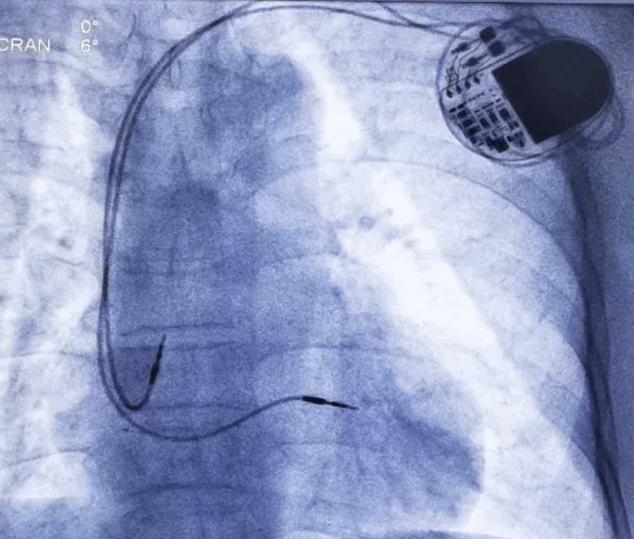

2. 起搏相关技术

(1)单/双腔心脏起搏器是起搏心房和/或心室肌,使心脏保持正常跳动,是治疗缓慢性心律失常的常规技术。

心脏起搏器安置术